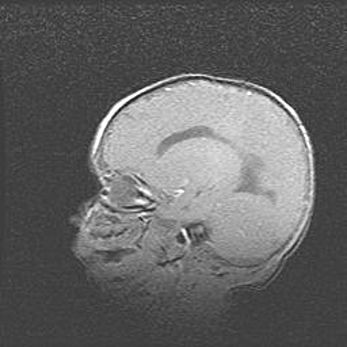

Наружная гидроцефалия с возможной атрофией височных областей.

Возраст: 28 дней

Вес: 3670 г

Пол: мужской

Окружность головы: 38 см

Срок гестации: 40 недель

Гидроцефалия головного мозга у новорожденных – это заболевание, которое характеризуется скоплением избыточного количества спинномозговой жидкости в желудочковой системе головного мозга в результате затруднения её перемещения от места выработки к месту поглощения в кровеносную систему или вследствие нарушения абсорбции. При открытой наружной форме гидроцефалии у новорожденных расширяются и переполняются субарахноидные пространства.

При нормотензивных  формах,  которые,  как  правило,  являются  следствием  перенесенных ишемических  повреждений  паренхимы  мозга,  возможно  сочетание микроцефалии  с нормотензивной гидроцефалией. В основе данных изменений лежит атрофия больших полушарий с преимущественной  локализацией  в  лобно-височных  областях.